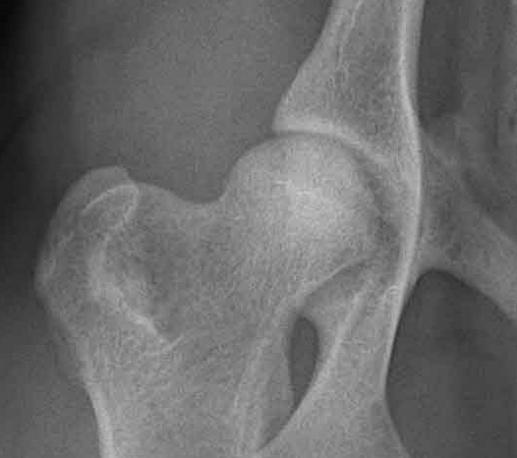

HD FRI: Røntgenbilde av normalt hofteledd som er HD-fri (A) uten forkalkninger.

Diagnosen stilles ved hjelp av klinisk undersøkelse og røntgenbilder som vurderer hofteleddets utforming og eventuell slitasje, med eller uten forkalkninger. Det finnes ulike grader av denne defekten, og røntgenavlesning av hofteleddene graderes i Norge (NKK/FCI) etter følgende skala: Fri (A, B), svak (C), middels (D) eller sterk (E) grad av HD.